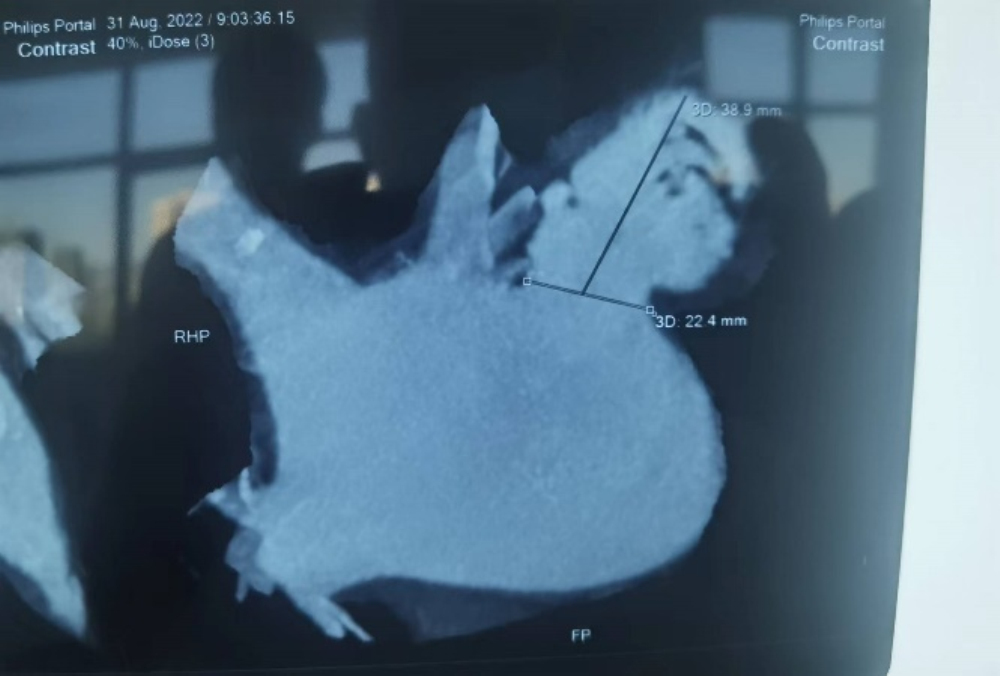

术前CT左心耳分析图

术前王智勇教授带领综合内科张薇副主任团队,邀请麻醉手术中心王彩霞主任、ICU谢秀峰副主任等多名专家进行了深入、细致的病例讨论。医学影像中心王宗博医师,为患者完成了术前左心耳CT造影检查,测量了左心房尺寸、明确肺静脉解剖状况,为手术的顺利完成做了充分的术前评估。经团队综合评估,计划为该患者在行冷冻球囊房颤消融术后,行左心耳封堵术预防卒中。